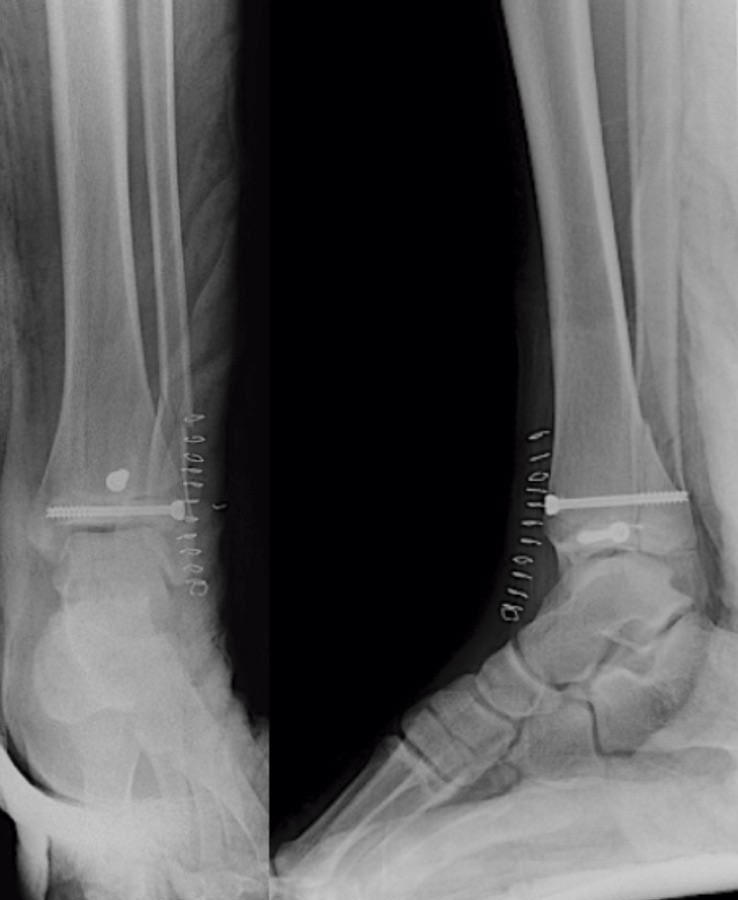

Se trata de un varón de 13 años de edad que acude a urgencias tras sufrir una caída y con eversión forzada del tobillo jugando al fútbol. A la exploración, presentaba inflamación en todo el tobillo izquierdo (región anterior y ambos maléolos) sin déficit neurovascular. En la radiografía simple se observó una fractura epifisiolisis de tipo IV (Figura 1).

Tras conseguir una adecuada reducción de la fractura, realizamos fijación interna con 2 tornillos canulados de rosca parcial de 16 mm (un tornillo epifisario de lateral a medial y otro metafisario anteroposterior) comprobando bajo fluoroscopio la reducción de la fractura (Figura 5).

A continuación, realizamos un cierre por planos meticuloso de la cápsula articular, retináculo extensor, subcutáneo y piel, inmovilizando con un yeso suropédico. El paciente presenta una evolución inmediata favorable con dolor controlado, exploración neurovascular normal y control radiológico inmediato correcto (Figura 6).

Figura 5. Control radiológico intraoperatorio: fijación con tornillos canulados.

Figura 6. Control radiológico postoperatorio.